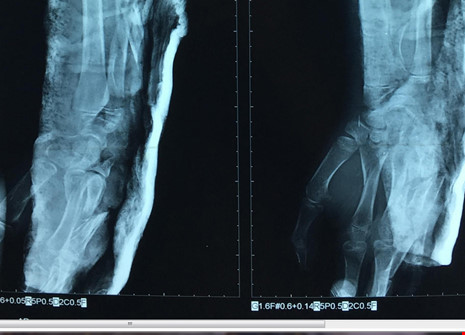

Kết quả chụp X-quang cho thấy xương tay trái của bệnh nhi T. bị gãy rất nhiều. Ảnh: VÕ KHÁNH

Chưa hết, bệnh nhi còn bị đứt nhiều tầng cơ tam đầu, dập đứt nhiều tầng toàn bộ cơ mặt sau cẳng tay. Bệnh nhi còn bị gãy nhiều tầng xương trụ, trật chỏm quay, gãy xương thuyền, xương cả, xương bàn ngón 4 và 5 tay trái. Người nhà cho biết bệnh nhi đi ghe rớt ngã xuống sông, chân vịt ghe máy cắt vào cẳng tay trái.